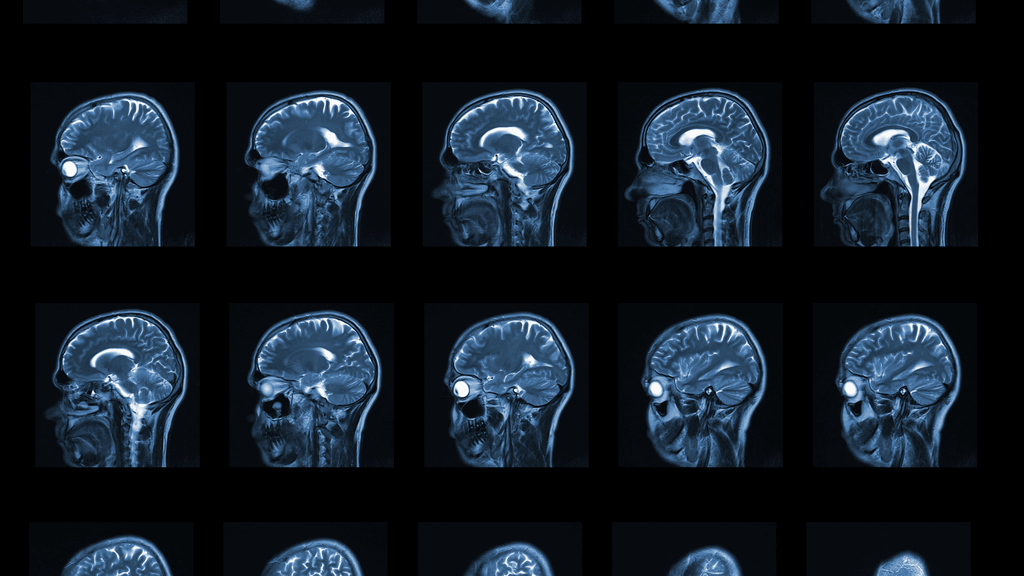

La microdescompresión vascular es la técnica quirúrgica de elección cuando hemos detectado una alteración estructural en el nervio tras la realización de un estudio de Resonancia magnética específico, sobre todo, con los actuales equipos de resonancia de alta resolución.

La alteración más frecuentemente vista en las pruebas de imagen es un contacto neuro-vascular entre el nervio y alguna arteria de la base del cráneo (más comúnmente la arteria cerebelosa superior). El contacto íntimo entre el nervio y el latido de la arteria, va generando una alteración crónica en las propiedades del nervio. La cirugía consiste en separar ambas estructuras (nervio y arteria) e interponer una membrana aislante entre ambas.